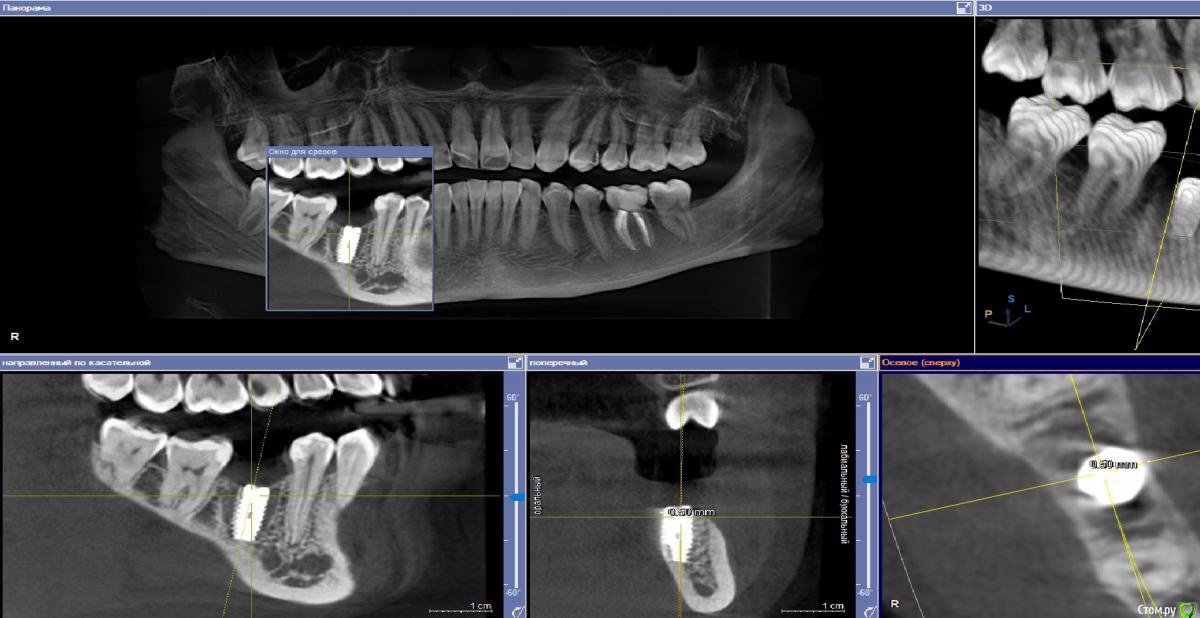

Ponchik Опубликовано 3 июля, 2018 Поделиться Опубликовано 3 июля, 2018 Вот как-то так блин получилось Весь из себя психованный ставил (дома поругался), а может по жизни косорукий, и вот.... язычная стенка 0.5-0.75 При запиле и вкручивании язычная стенка вела себя хорошо. Видел её язычно на 5-6мм вниз точно.Опыта мало, не знаю как поступить. Может вызвать пациентку и выкрутить его ? Ссылка на комментарий

TIGER Опубликовано 3 июля, 2018 Поделиться Опубликовано 3 июля, 2018 1.jpg Вот как-то так блин получилось Весь из себя психованный ставил (дома поругался), а может по жизни косорукий, и вот.... язычная стенка 0.5-0.75 При запиле и вкручивании язычная стенка вела себя хорошо. Видел её язычно на 5-6мм вниз точно.Опыта мало, не знаю как поступить. Может вызвать пациентку и выкрутить его ?БУДЕТ жить,не переживайте Ссылка на комментарий

Ponchik Опубликовано 3 июля, 2018 Автор Поделиться Опубликовано 3 июля, 2018 (изменено) https://photos.google.com/photo/AF1QipPJXDLEMrh16Or_6JOOJ6cuWlvGx85mMav8Tow_ Ссылка на "прокрутку КТ" 17сек. видео Изменено 3 июля, 2018 пользователем Ponchik Ссылка на комментарий

Ethan Hunt Опубликовано 4 июля, 2018 Поделиться Опубликовано 4 июля, 2018 я бы выкрутил в тот же момент. В области этого зуба, как правило, необходима ангуляция в пределах до 20 градусов. Нагрузите имплантат - может пойти резорбция язычно. Может и не пойти...выбирать вам Ссылка на комментарий

Реваз Опубликовано 4 июля, 2018 Поделиться Опубликовано 4 июля, 2018 лучше конечно выкрутить, вероятность резорбции большая Ссылка на комментарий

Тимур86 Опубликовано 4 июля, 2018 Поделиться Опубликовано 4 июля, 2018 (изменено) Вообще проблемы не вижу. Как и раньше говорил-если после всех имплантов все КТ будут делать,то устанем имланты выкручивать))десны добавить и всё хорошо будет Изменено 4 июля, 2018 пользователем Тимур86 5 Ссылка на комментарий